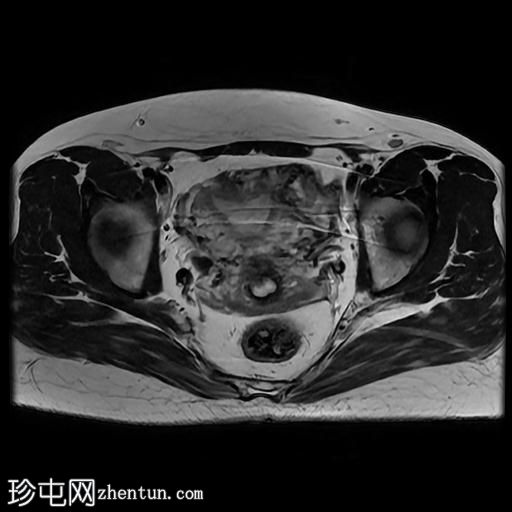

轴位

T1加权像

盆腔MRI显示双侧子宫旁多条迂曲静脉,自子宫肌层延伸至盆腔。

此外,左侧附件可见两个充满液体的单纯性囊肿,大小分别约为31 mm和32 mm;右侧附件可见一个卵泡囊肿,大小约为19 mm。

影像学特征符合盆腔充血综合征的诊断,患者为35岁女性,有慢性盆腔疼痛和痛经病史。